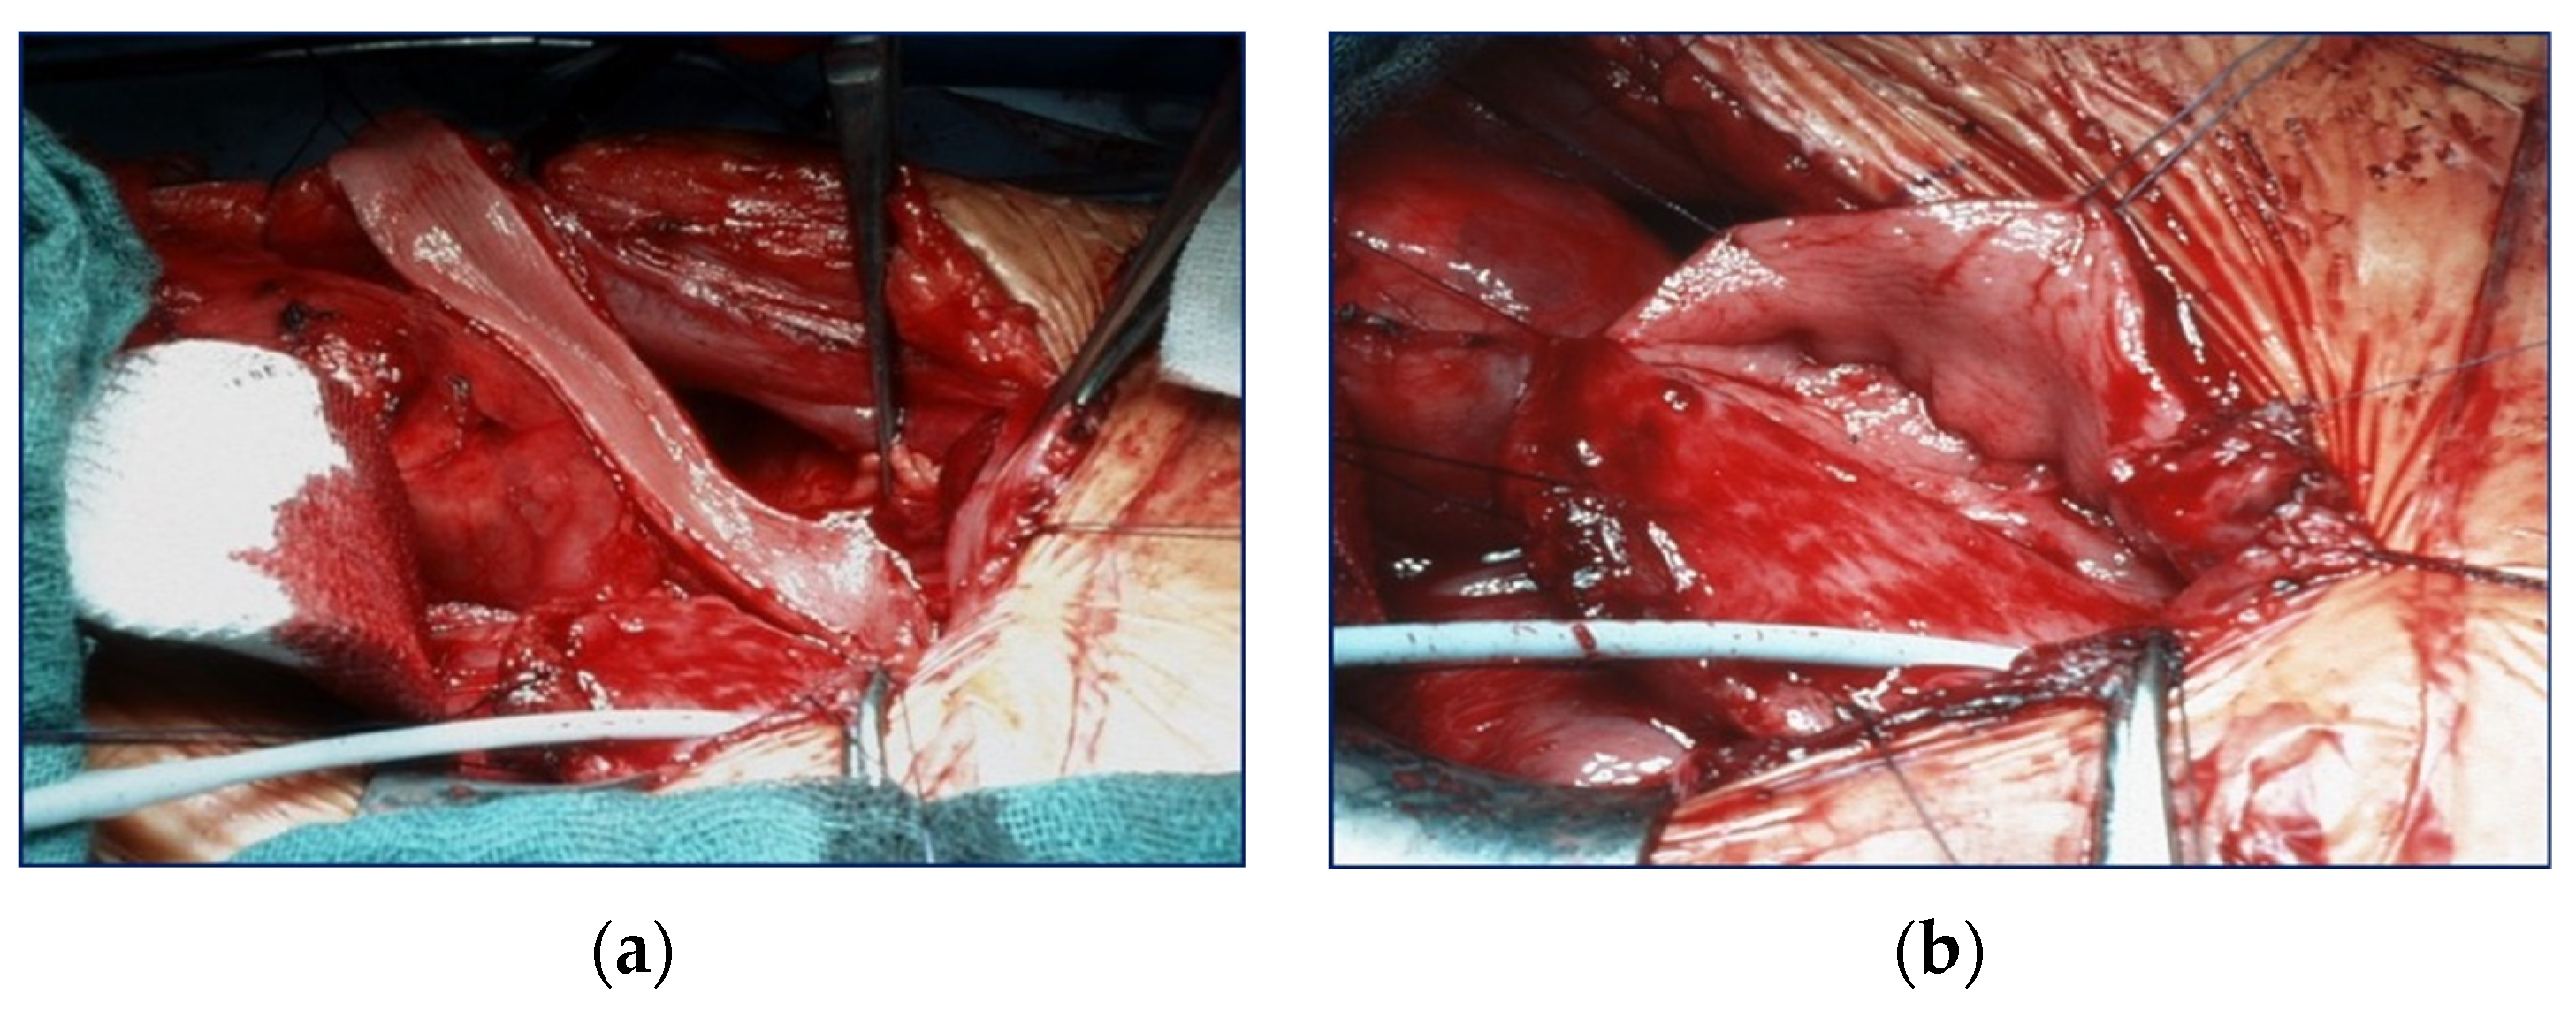

If necessary, the patient simultaneously received a continent (Mitrofanoff-stoma) or incontinent (vesicostomy) stoma as well as an antireflux plasty (ARP) of the contralateral ureter. Two patients had received a kidney transplant prior to UCP, while three patients were augmented in preparation for a transplant. Detailed information is shown in Figure 2.